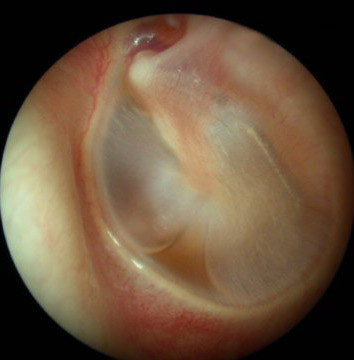

Notice the different shades of color yet the eardrum still remains an opaque translucent appearance in all the pictures

Acute Infection with bulging of the tympanic membrane due to pressure from purulence (pus) behind it. The last picture reveals an ear tube that has gotten prematurely blocked and the ear is once again infected.